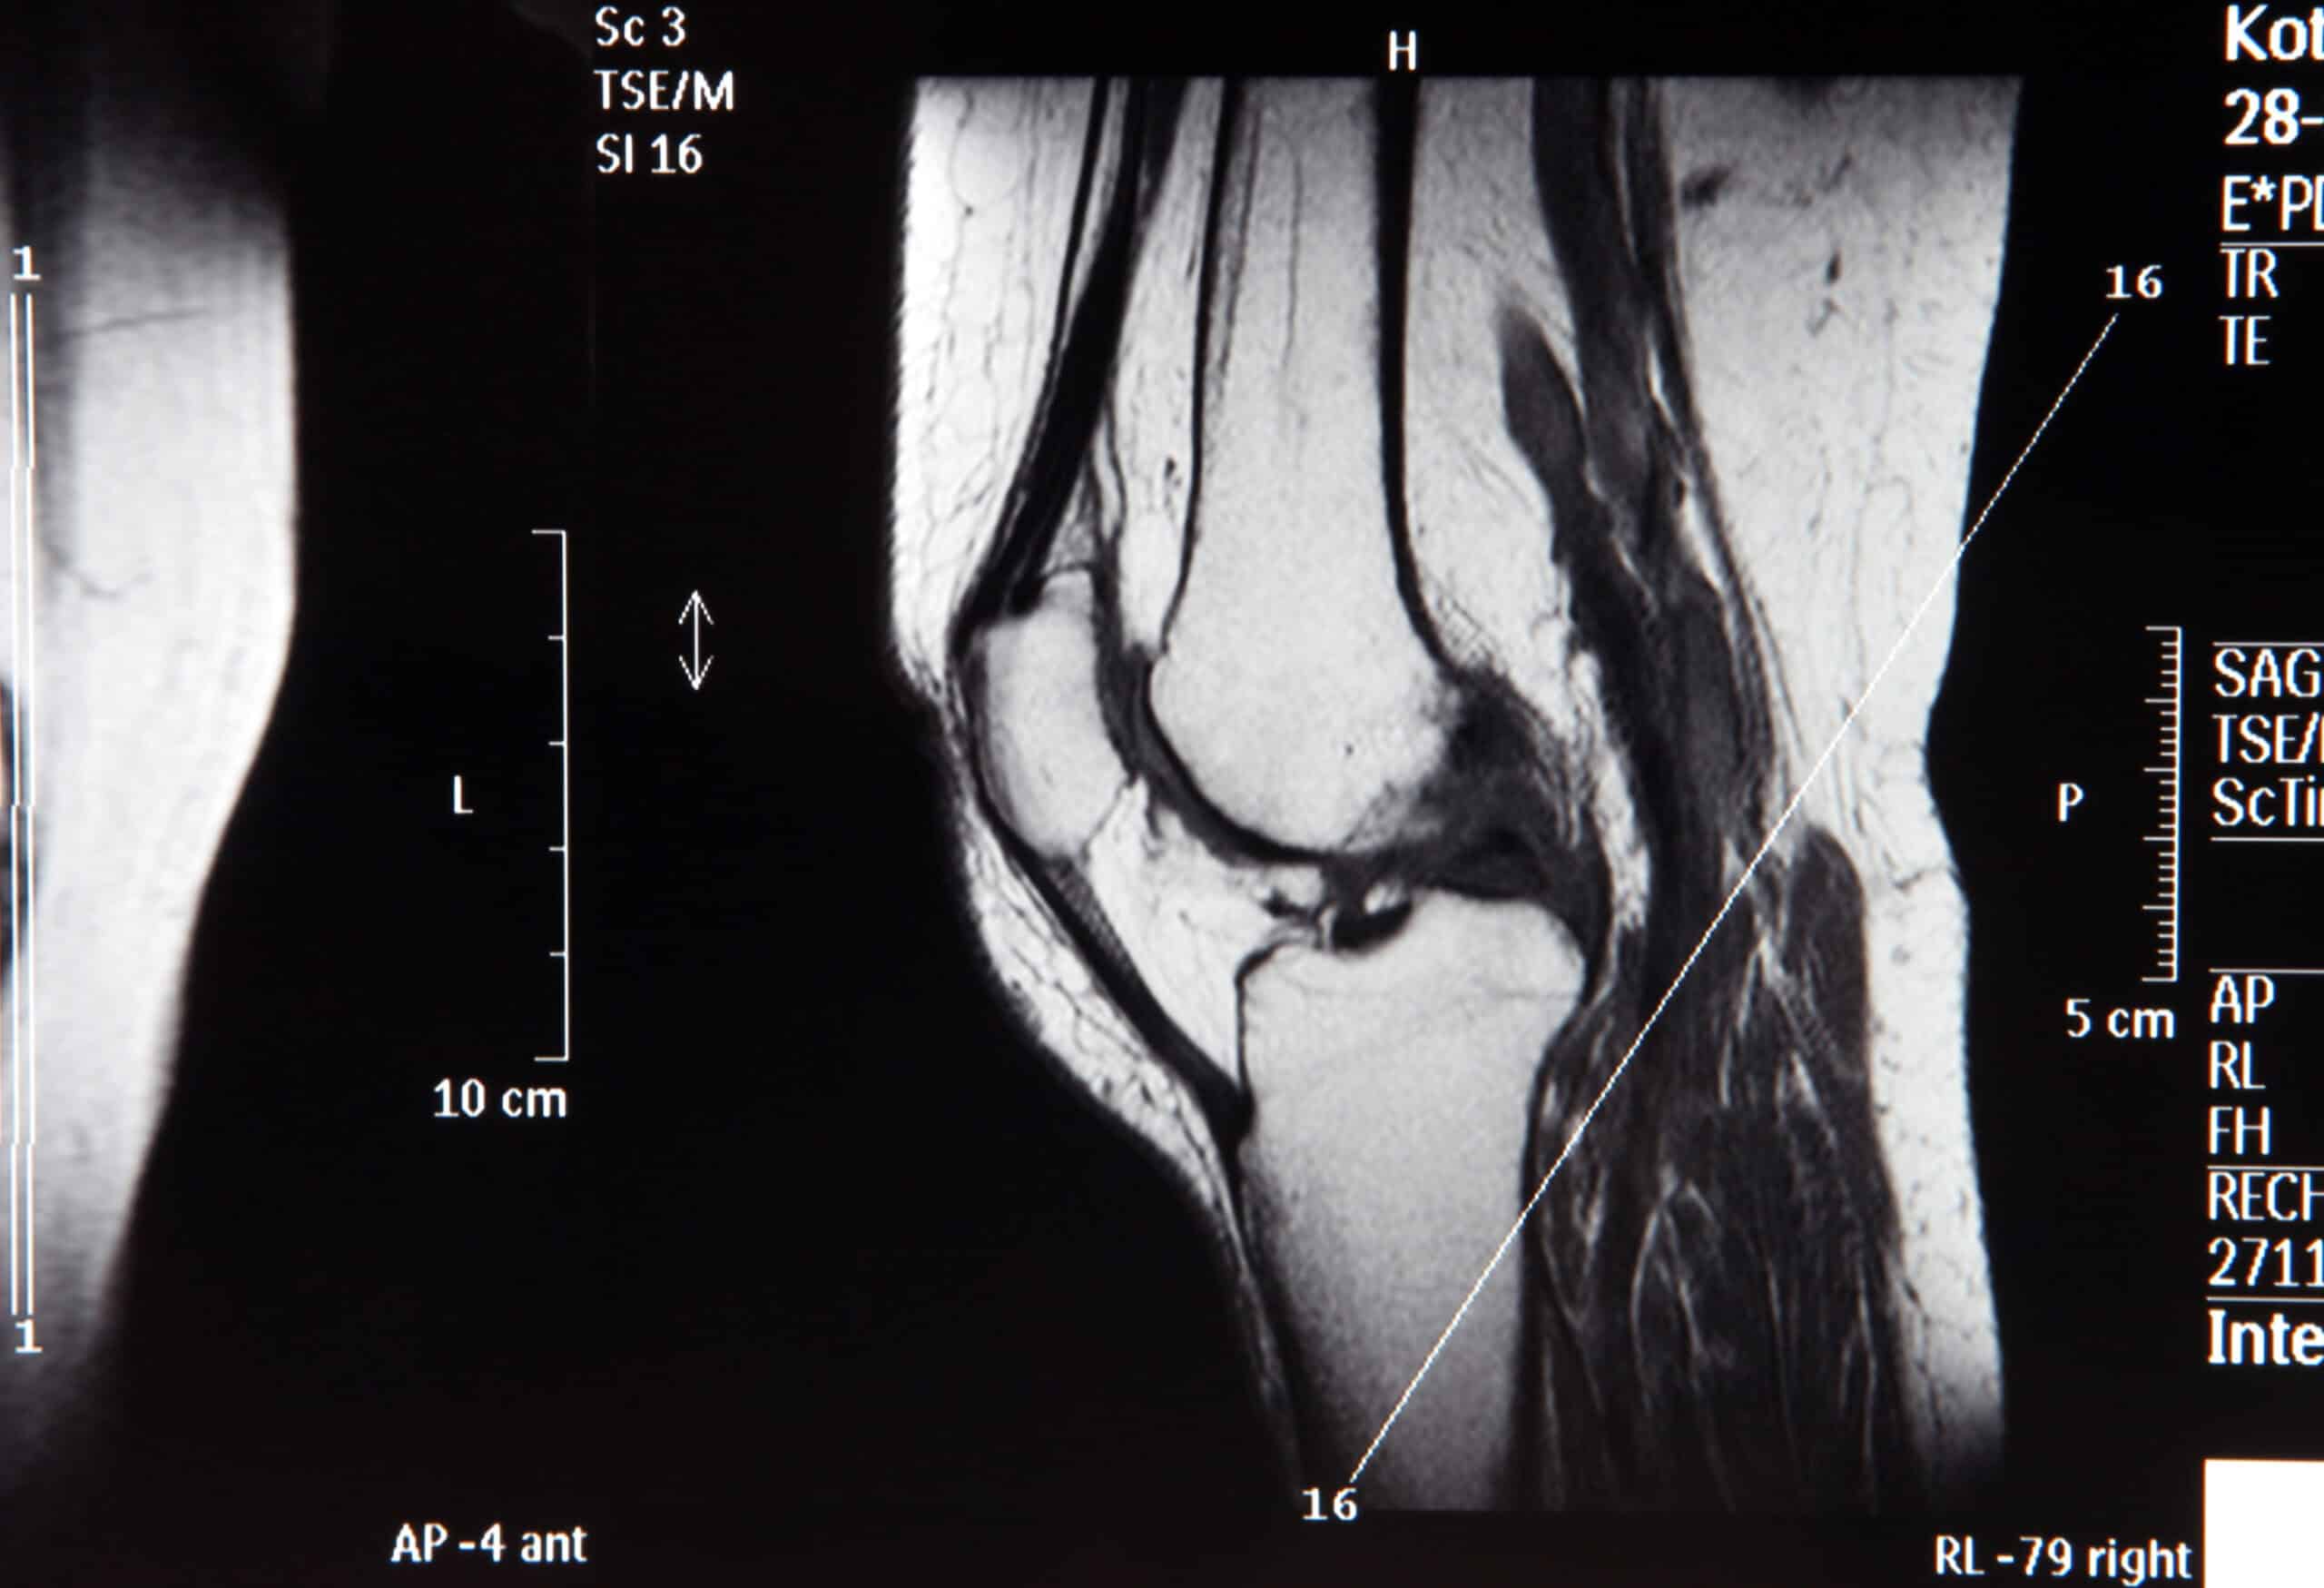

في التجارب التي أُجريت على الفئران، أظهر العلاج نتائج واعدة، حيث زادت سماكة غضروف الركبة المتآكل، وتحسنت القدرة على المشي والحركة، كما انخفضت مؤشرات الألم. بالإضافة إلى ذلك، تم منع تطور الخشونة بعد إصابات مشابهة لتمزق الرباط الصليبي، مما يعكس فعالية العلاج.

تجدر الإشارة إلى أن الباحثين قاموا أيضًا باختبار العلاج على عينات غضروف بشري مأخوذة من مرضى خضعوا لعمليات تبديل مفصل الركبة، حيث ظهرت مؤشرات مشجعة على تجدد النسيج وانخفاض الالتهاب. هذه النتائج تعزز الأمل في إمكانية تطبيق هذا العلاج على البشر في المستقبل القريب.

إذا أثبتت التجارب البشرية نجاحها، فقد يصبح استبدال الركبة أو الورك خيارًا أقل شيوعًا مما هو عليه اليوم. هذا الاكتشاف يمثل تحولًا جذريًا في كيفية التعامل مع التهاب المفاصل، حيث يمكن أن يؤدي إلى تطوير علاجات أكثر فعالية واستدامة.